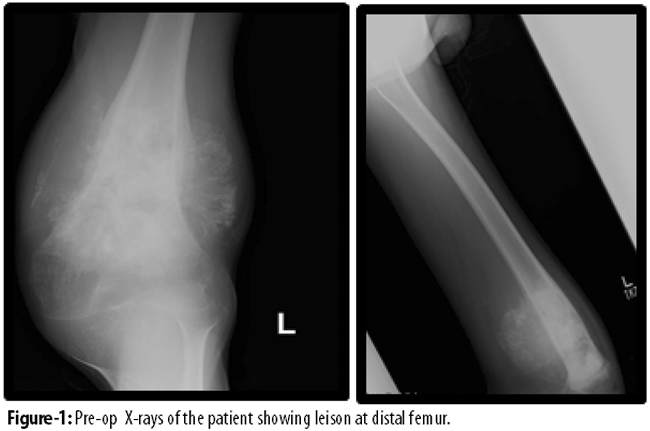

Van Nes Rotationplasty for locally advanced lower extremity tumours. A reterorespective audit was conducted at Aga Khan University Hospital (AKUH), Karachi, and comprised cases of bone and soft tissue sarcoma that underwent Van Ness Rotationplasty over seven years from January 2005 to December 2011. Demographic data, family history, past history, co-morbids, date since diagnosis, duration of symptoms, type of tumour, metastasis, pre-op and post-op functional status, recurrence and survival were collected. The preoperative work-up included routine radiographs, bone and soft-tissue scintigraphy, magnetic resonance imaging (MRI) of the lesion and computed tomography (CT) scan of the chest.

Patients were kept in house for 5 to 6 days postoperatively. Drains were not used. On day 12 stitches were removed. When the wound got healed and bone ends were progressing well, the patients were fitted with external prosthesis and encouraged to walk usually at 6 weeks. The patients were followed up regularly in the outpatient department (OPD) for a period ranging from 6 months to 34 months (Figures 1-5).

Of the 351 cases of bone and soft tissue sarcoma, 9(2.6%) underwent Van Ness Rotationplasty and were included in the study; 5(55.6%) females and 4(44.4%) males. Age ranged from 7 to 39 years with a mean of 15±2SD years. The mean duration of symptoms was 7±3 SD months (range: 8-41 months). Eight (88.9%) were osteogenic sarcomas, and 1(11.1%) had squamous cell carcinoma of knee. Besides, 8(88.9%) involved distal femur. Overall, 7(77.8%) had localised Enneking stage IIB disease.